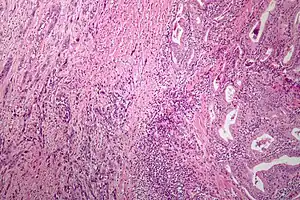

Microscopic image of anaplastic thyroid carcinoma. H&E stain.

Anaplastic tumors have a high mitotic rate and frequently invades the local blood and lymphatic vessels.[5] Cellular death is frequently visualized on microscopic images.[2] The presence of regionally swollen lymph nodes in older patients in whom needle aspiration biopsy reveals characteristic vesicular appearance of the nuclei supports a diagnosis of anaplastic carcinoma. Microscopic images of ATC usually show inflammatory cells from the immune system such as T cells and macrophages.[2]

On immunohistochemistry testing, ATC is usually positive for the keratin, p53, and PAX8 proteins and is negative for thyroid transcription factor-1, thyroglobulin, and calcitonin.[2] ATC cells demonstrate high levels of PD-L1 expression.[2] BRAF and TERT mutations are seen more commonly in ATC than in differentiated thyroid cancer.[2]